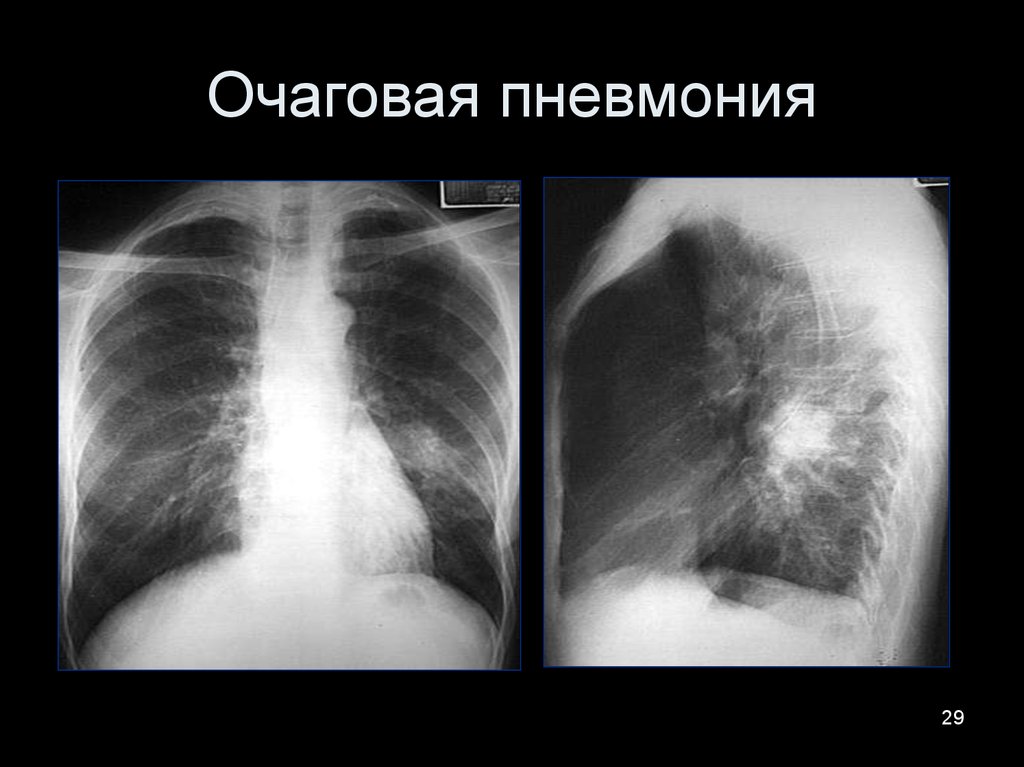

Очаговая пневмония